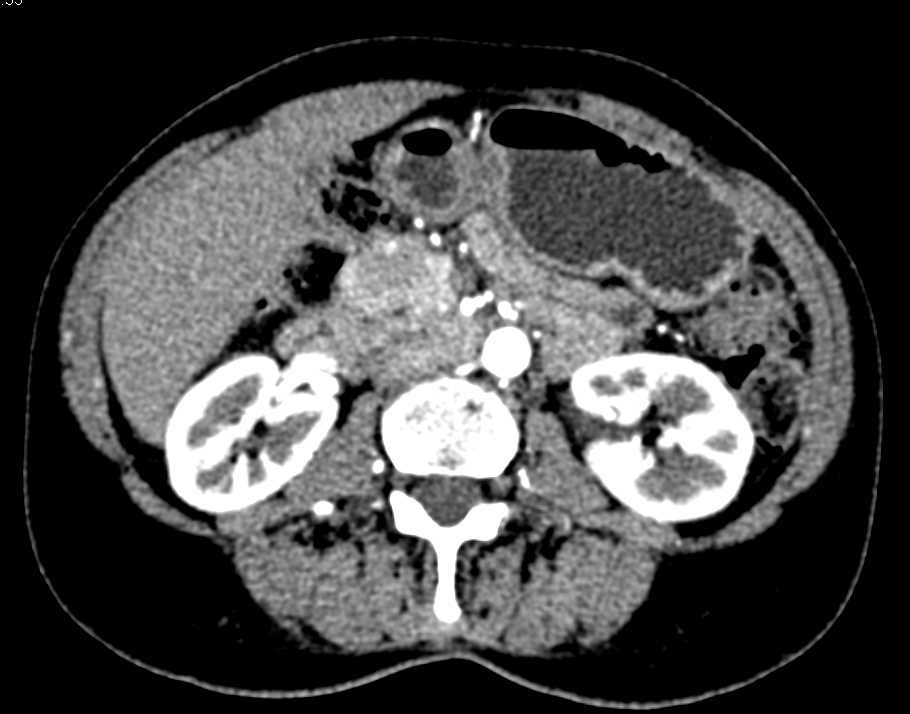

Intraductal Papillary Mucinous Neoplasm (IPMN) with High Grade Dysplasia